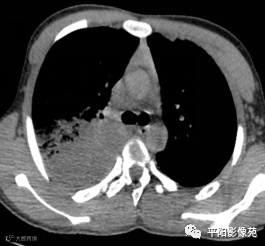

入院CT:

影像特征:X线片右肺中上野片状高密度影,下缘以叶间裂为界,上缘及外侧缘模糊;CT位于右肺上叶后段,呈片状实变影,内见支气管影,边缘模糊。

影像诊断:右肺上叶大叶性肺炎。